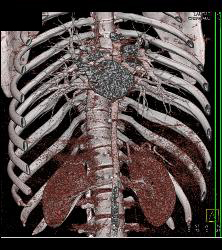

Small Caliber Aorta With Hardware Screw Abutting Aorta